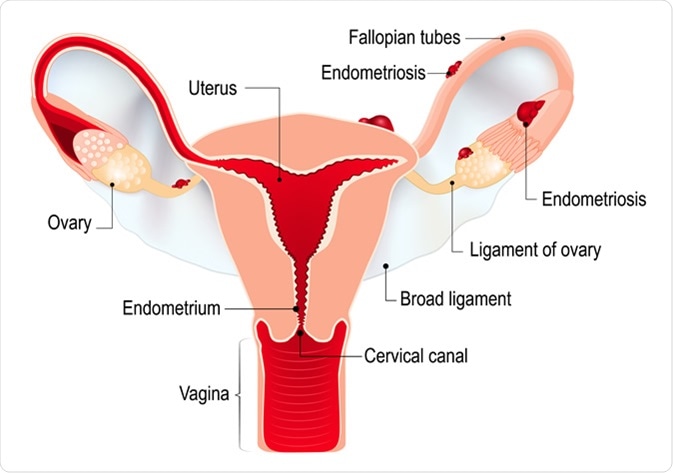

Endometriosis

Endometriosis is a painful condition wherein the tissue that normally lines the endometrium grows outside the uterus. It can grow in the fallopian tubes, ovaries, and the tissue lining the pelvis. The pain occurs before, during, or after menstruation. Some women may feel disabling severe pain. It can also happen during or after sexual intercourse, urination, or bowel movements.

Endometriosis. Schematic drawing of various types of endometriosis disease. Image Credit: Designua / Shutterstock